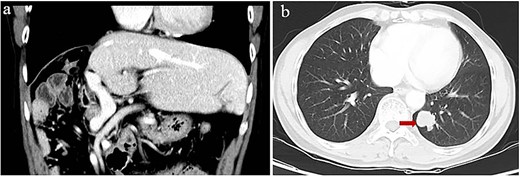

Starting 1 month after repeat surgery, the patient received 200 mg of the ICI tislelizumab (BGB-A317; BeiGene, Beijing, China) once every 3 weeks via intravenous delivery lasting 60 min, in accordance with the manufacturer’s recommended dosing schedule. From 8 weeks on this therapy onwards, the level of alpha-fetoprotein in serum progressively increased. After 74 weeks on this therapy (21 treatments), the patient was diagnosed with Grade 2 hypothyroidism based on levels of thyroid hormone in serum and with Grade 2 pruritus based on signs and symptoms. Hypothyroidism was not treated because there were no obvious symptoms. However, he showed no signs of intra- or extrahepatic metastases in the entire body, abdomen, thoracic cavity, or brain based on magnetic resonance imaging or on contrast-enhanced, positron-emission, or bone-emission computed tomography. After 24 weeks on tislelizumab, a single metastasis was detected in the lung (Fig. 3). The patient was subjected to eight cycles of stereotactic body radiation therapy, and the level of alpha-fetoprotein in serum 3 weeks later was 275 ng/ml. Intensive follow-up continues.

Computed tomography of lung metastasis after 2 years of adjuvant ICI. (a) Imaging at the venous stage did not reveal obvious lesions in the residual liver. (b) Imaging of the left lower lung revealed a single tumor (arrow).